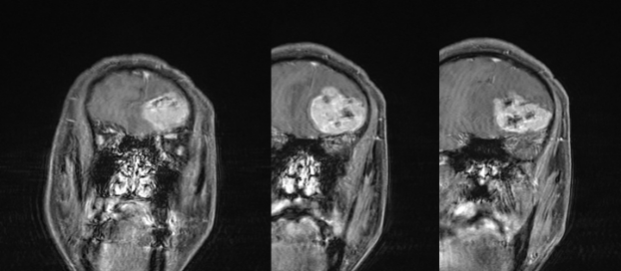

CASE 3

女,60 岁

右侧顶部低信号占位,边界清晰,增强可见边缘轻度强化;外院 CT 示高密度占位。

诊断:沙粒型脑膜瘤